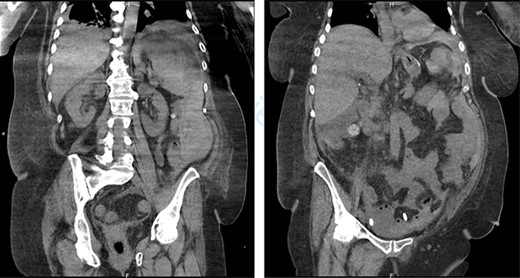

On the sixth post-operative day, the patient suddenly felt weak. She presents with pallor, hypotension and tachycardia. We noticed some blood in the left drain. We immediately started a fluid resuscitation and performed an urgent CT which showed a fresh 6-cm wide splenic sub capsular hematoma associated with a major hemoperitoneum (Fig. 2).